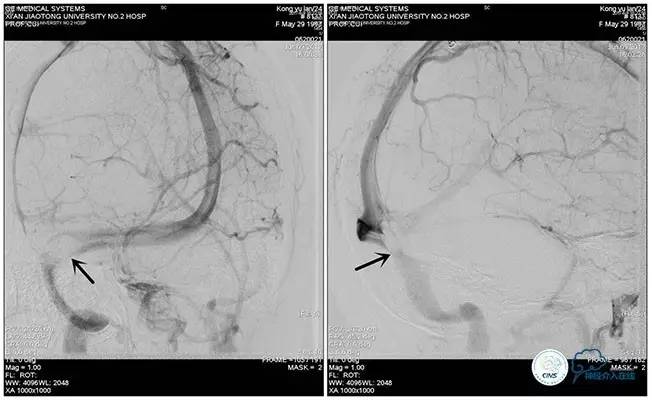

右侧ICA造影正侧位

右侧ICA造影斜位

右侧ICA正侧位

右侧ICA斜位

静脉淤滞

左侧ICA斜位

左侧VA正斜位